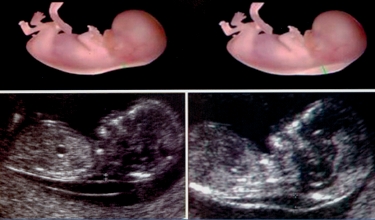

2. การตรวจคลื่นเสียงความมถี่สูง เพื่อวัดความหนาบริเวณต้นคอของทารกในครรภ์

ถ้ามีน้ำสะสมอยู่บริเวณต้นคอทารกอายุครรภ์ 10-14 สัปดาห์ (บาง = เสี่ยงต่ำ / หนา = เสี่ยงสูง)